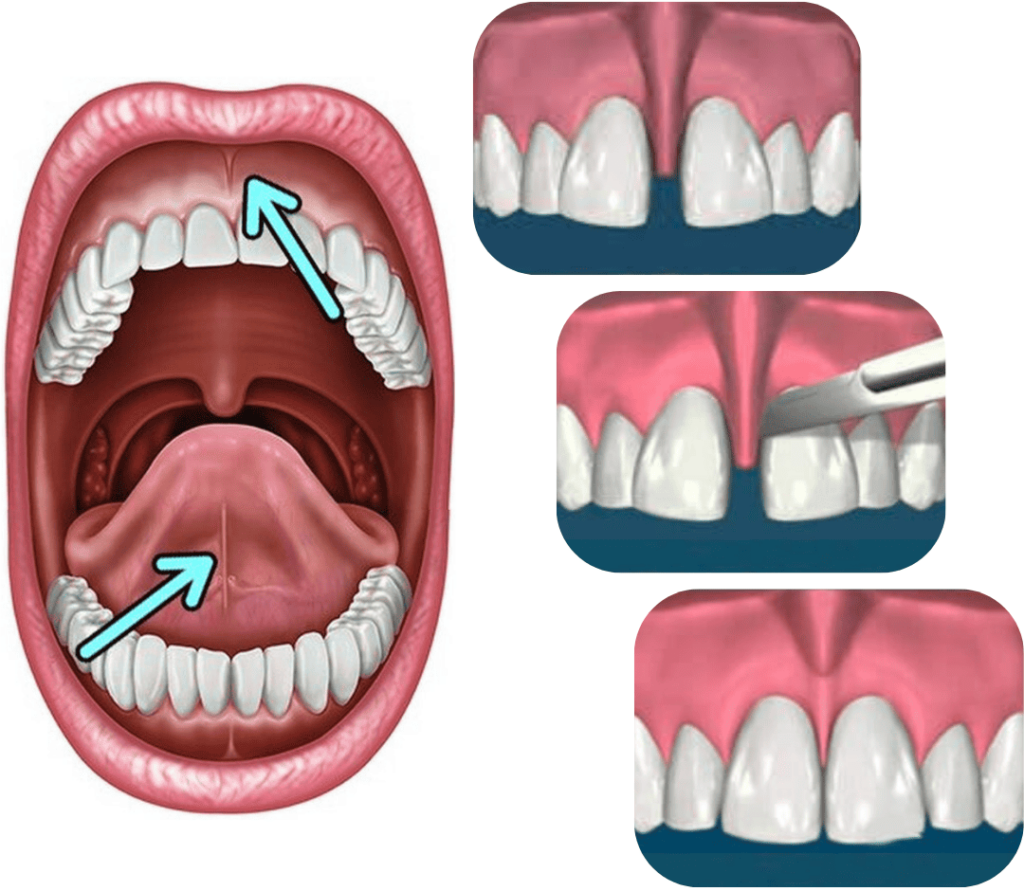

FRENULECTOMY

Frenulectomy is an oral surgical procedure in which the frenulum – the small fold of tissue located beneath the upper lip or tongue – is released.

The frenulum in the lower jaw can restrict tongue movement and impair speech, while in the upper jaw it can cause a gap between the front teeth (diastema) or gum recession.

The procedure is simple, painless, and brief.

The procedure is performed under local anaesthesia, and recovery is rapid and painless.